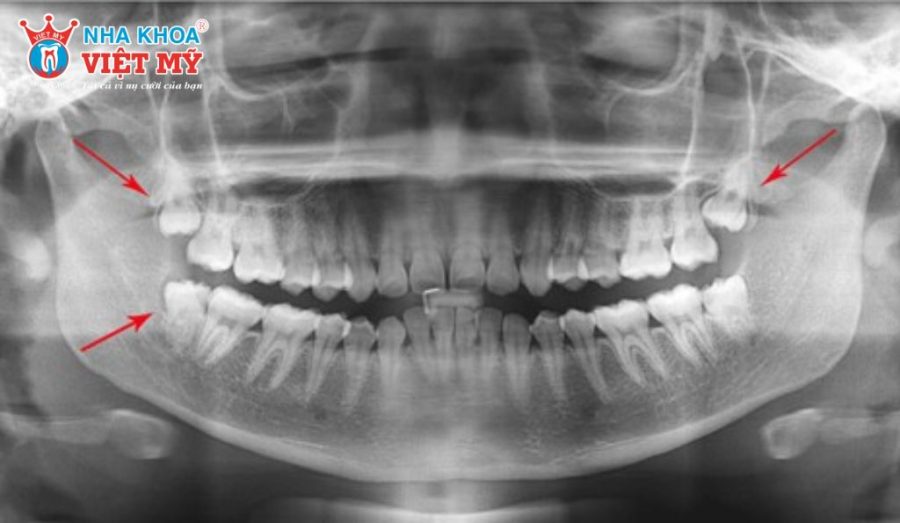

Về mặt giải phẫu, răng khôn hàm trên có thể có từ 2 đến 4 chân răng với hình dạng cong và phân nhánh phức tạp khiến việc nhổ bỏ trở nên khó khăn hơn so với răng khôn hàm dưới. Chính vì vậy, trước khi can thiệp, bác sĩ thường chỉ định chụp X-quang để đánh giá chính xác vị trí cũng như hình thái chân răng từ đó đưa ra phương án điều trị an toàn.

Răng khôn hàm trên mọc lệch hoặc mọc ngầm thường không thể quan sát rõ bằng mắt thường. Tuy nhiên, khi có cảm giác vướng víu, đau lan sang răng số 7 hoặc khó nhai về một bên, đó có thể là dấu hiệu cảnh báo. Bạn cần đến ngay cơ sở nha khoa uy tín để chụp X-quang để giúp xác định chính xác tình trạng này.